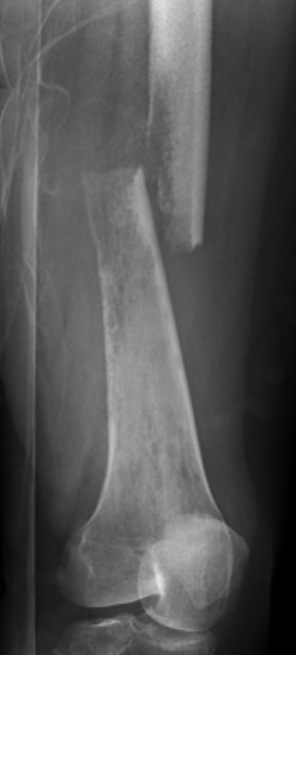

Describe the type of fracture depicted [1]

Subtrochanteric fracture

This fracture passes distal to the trochanters

The femoral neck remains intac